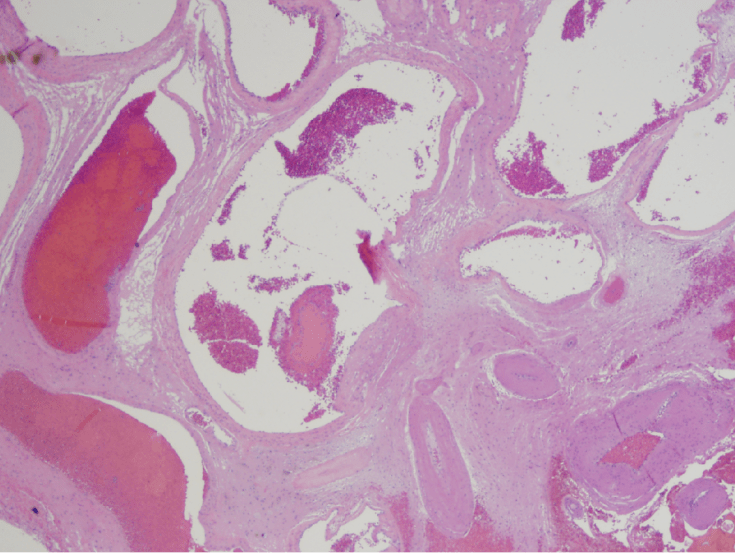

Arteriovenous malformation, or AVM, is a collection of abnormal vessels that lack an intervening capillary bed and are separated by gliotic brain tissue. Some vessels have thick walls with elastic laminae typical of arteries, while others have thin collagenous walls typical of veins. In addition, “arterialization of a vein” can also be seen in which a vessel that lacks an elastic lamina (i.e. a vein) has very thick walls like an artery. Some vessels may have thrombi due to disturbed blood flow through the abnormal vessels, a feature that can be seen on imaging.